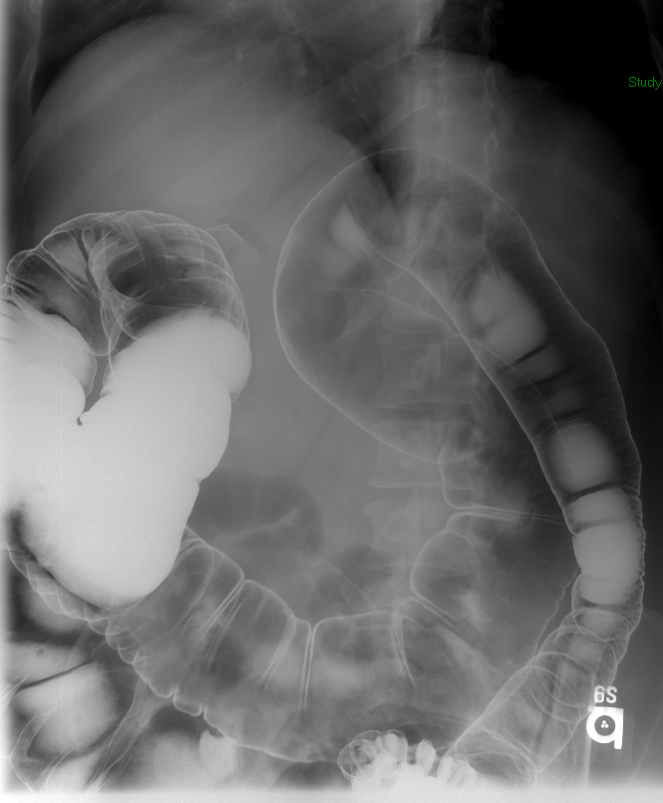

- The technologist will obtain a scout radiograph (key image 1). Assess the radiograph for any possible contraindications to performing the examination.

- Proceed to instill contrast material into the colon until the contrast material has reached the cecum and the colon appears fully distended.

- It may be necessary to move the patient into different positions to facilitate the progression of contrast material

- Intermittently look with the fluoroscope while the contrast material moves through the colon. As areas of the colon become distended with contrast material, obtain spot images

(key image 6)

(key image 7)

(key image 8)

(key image 9).

- Be sure obtain images of the entire contrast material filled colon.

- Once you have obtained spot images of the entire colon, the technologist will then obtain the post study overhead radiographs:

- AP or PA position to include the entire colon. PA is preferable if the patient can tolerate (it may be necessary to take more than one image to image the whole colon)

(key image 12)

(key image 13).